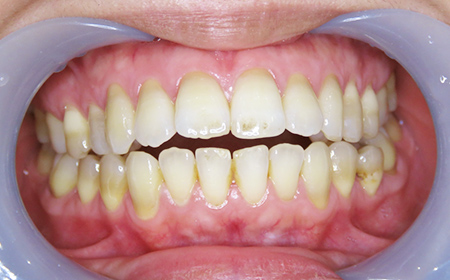

CASE02

Before

After

| 施術名 |

インビザラインGoを用いた矯正治療(叢生) |

| 治療期間 |

4ヶ月 |

| 治療費 |

437,800円(税込) |

| リスク |

マウスピース装置により疼痛・咬合時痛を生じる事があります。割れたり壊れたりする事があります。 |

歯科医師からのコメント

人と話す機会の多いご職業で、以前より「前歯のがたつき」が気になるとのことでご相談にいらっしゃいました。仕事中も目立たず、仕事に支障がでなくてよかったと仰っており、とても満足しておられました。